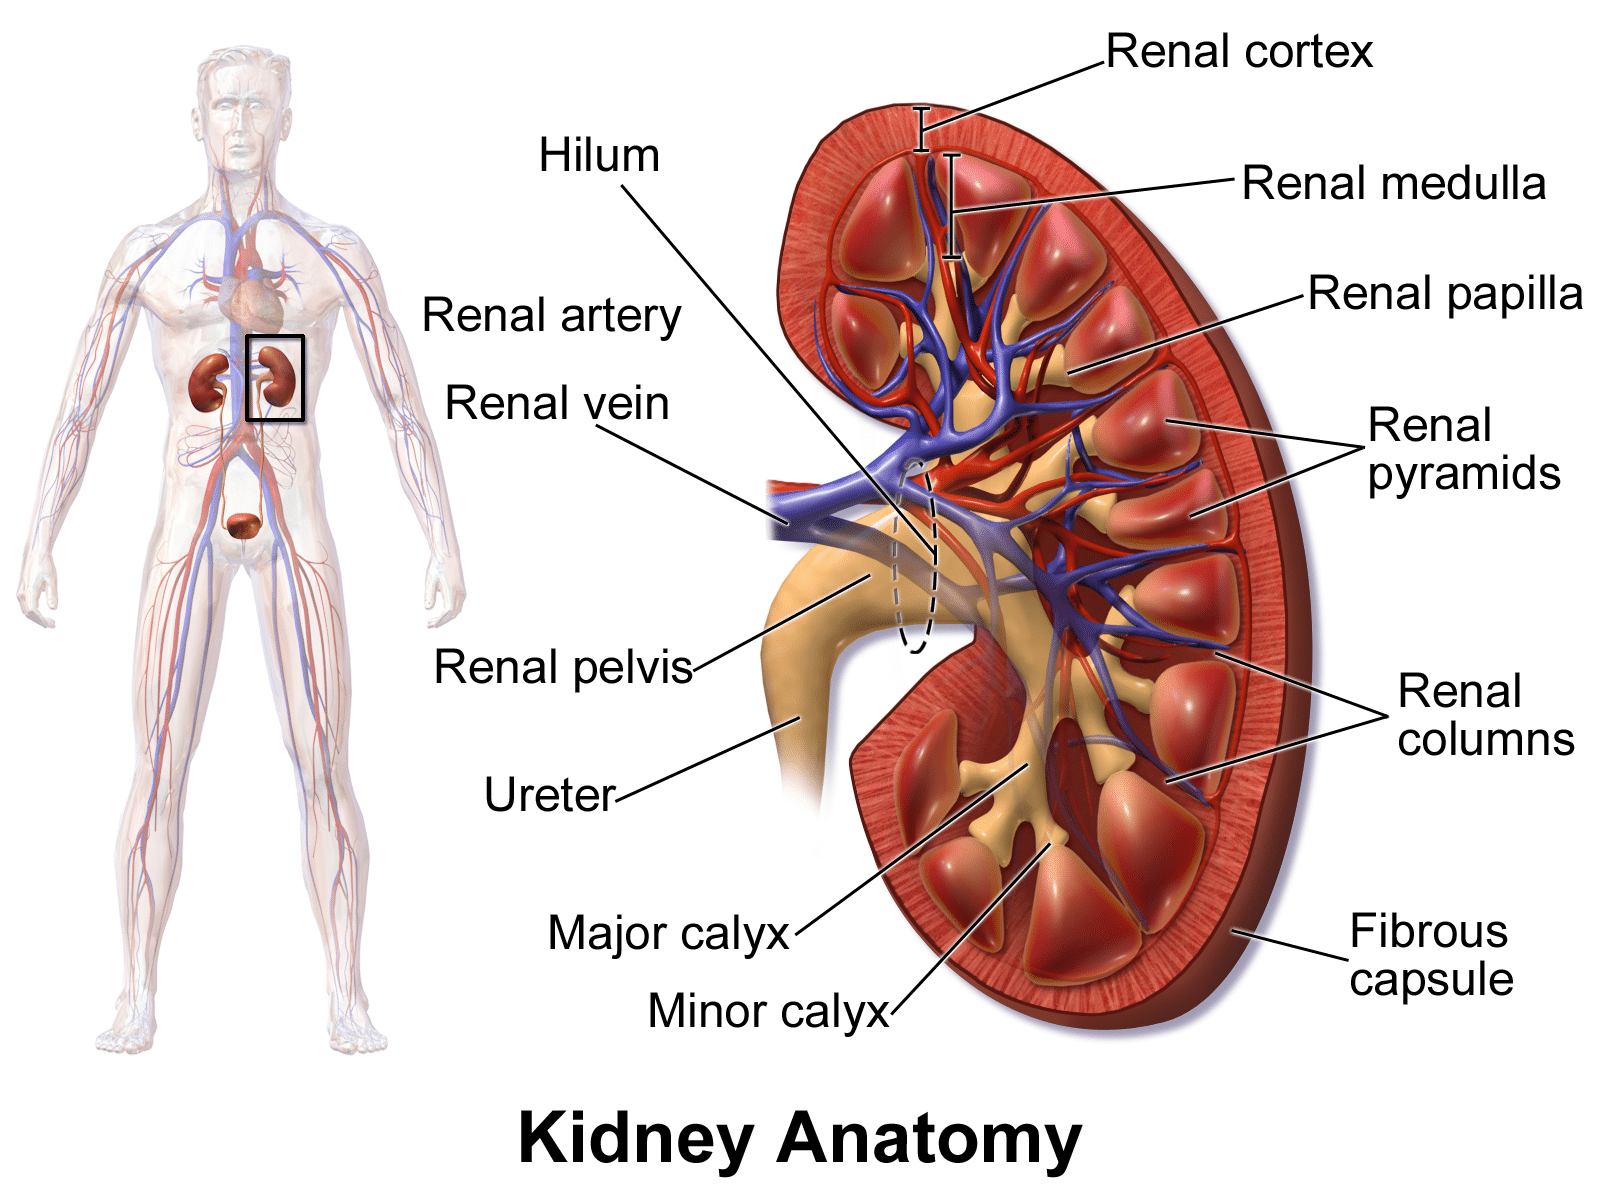

Οι πιο συχνές επιπλοκές που σχετίζονται με το Covid-19 ήταν πνευμονία, αναπνευστική ανεπάρκεια, νεφρική ανεπάρκεια και σήψη ή συστηματική φλεγμονή, σύμφωνα με άλλες μελέτες. Ο απόλυτος κίνδυνος κάποιου ατόμου με Covid-19 να έχει αυτές τις σοβαρές καταστάσεις ήταν 27,6% για πνευμονία, 22,6% για αναπνευστική ανεπάρκεια, 11,8% για νεφρική ανεπάρκεια και 10,4% για σήψη ή συστηματική φλεγμονή. Οι ερευνητές βρήκαν επίσης συσχετίσεις με μια σειρά από άλλες πνευμονικές και καρδιαγγειακές παθήσεις, όπως διαταραχές πήξης του αίματος και φλεγμονή της καρδιάς, αν και ο κίνδυνος αυτών ήταν σχετικά χαμηλός. Σε αντίθεση με τα αποτελέσματα άλλων μελετών, ο Covid-19 δεν φάνηκε να σχετίζεται με υψηλότερο κίνδυνο εγκεφαλικού επεισοδίου.